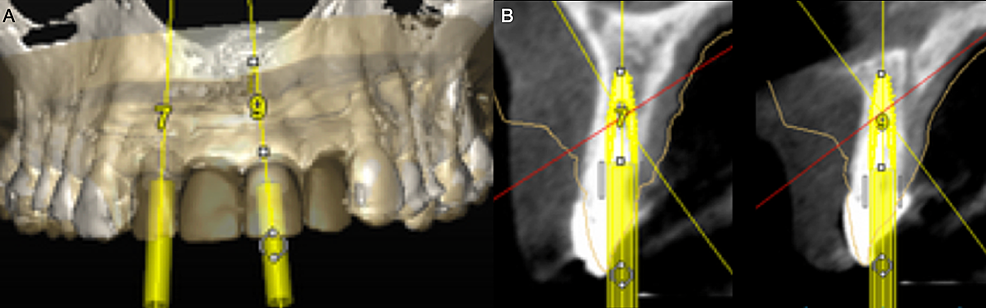

The implant was planned using implant software after the soft tissue’s desired shape was achieved (SimPlant, Dentsply Sirona Implants Inc, York, PA, USA) (Figure 6). Two implants at the maxillary right lateral incisor and maxillary left central incisor sites were planned to support a dental prosthesis from the maxillary left lateral incisor to the right lateral incisor. These sites were chosen based on the condition and thickness of the bone in the incisor region. Two weeks after the soft tissue contoured, the implant surgery was performed with a palatally-oriented crestal incision and bilateral sulcular incisions on the canines to reflect a full mucoperiosteal flap. The incision lines for the surgical flap were placed to avoid damaging the soft tissue line created during the preparation. Two bone-level implants of size 4.1mm (BLT RC, Straumann Group, Basel, Switzerland) were inserted (Figure 7A). For primary soft tissue closure, a simple interrupted suture technique (Polysyn FA, Surgical Specialties Corporation, Wyomissing, PA, USA) was used (Figure 7B, 7C). The implants were not loaded, and the existing fixed provisional restoration was cemented back onto the canines. During the two months of osseointegration, the provisional restorations maintained the soft tissue architecture that had been previously obtained.